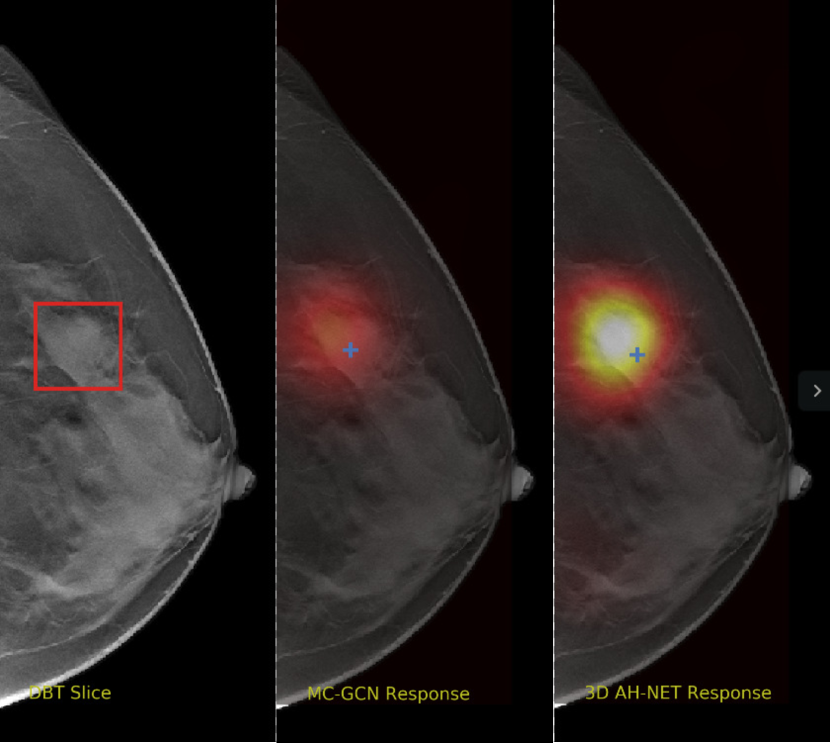

We selected some example slices from the DBT dataset to demonstrate the advantage of our proposed AH-Net for the Breast cancer screening. From Fig. 8 to Fig. 12, we show slices from five test DBT volumes that both the MC-GCN and the proposed 3D AH-Net could successfully detect the suspected breast lesion. The original DBT slice is shown on the left with the lesion annotated by our radiologist. Please note the original annotation is a 3D box. The figures in the middle and on the right are response maps from MC-GCN and 3D AH-Net overlaid on the original image, respectively. The detection locations obtained with non-maximal suppression are displayed with cross markers. As shown in the images, the proposed network can detect breast lesions varying in sizes and appearances. The confidence of the 3D AH-Net is usually higher than that of MC-GCN. From Fig. 13 to Fig. 17, we show five volumes that MC-GCN failed to detect the lesions since the lesions were not distinguishable from other breast tissues using the information within the slice. In contrast, 3D AH-Net was able to detect the lesions from such volumes using the 3D context between slices. As shown in Fig. 18 to Fig. 22, there are also volumes with lesions that both network failed to detect. Such lesions normally reside in the dense breast tissues. The boundary between these lesions and the normal breast tissues usually have low contrast. The networks sometimes also confuse them with other roundish structures in the breast such as lymph nodes or skin moles.

Figure 8: Example DBT slice 1 with a lesion that can be detected by both MC-GCN and 3D AH-Net. Though the lesion is blended in the dense breast tissues, our network is able to detect it according to the speculations around the lesion boundary.